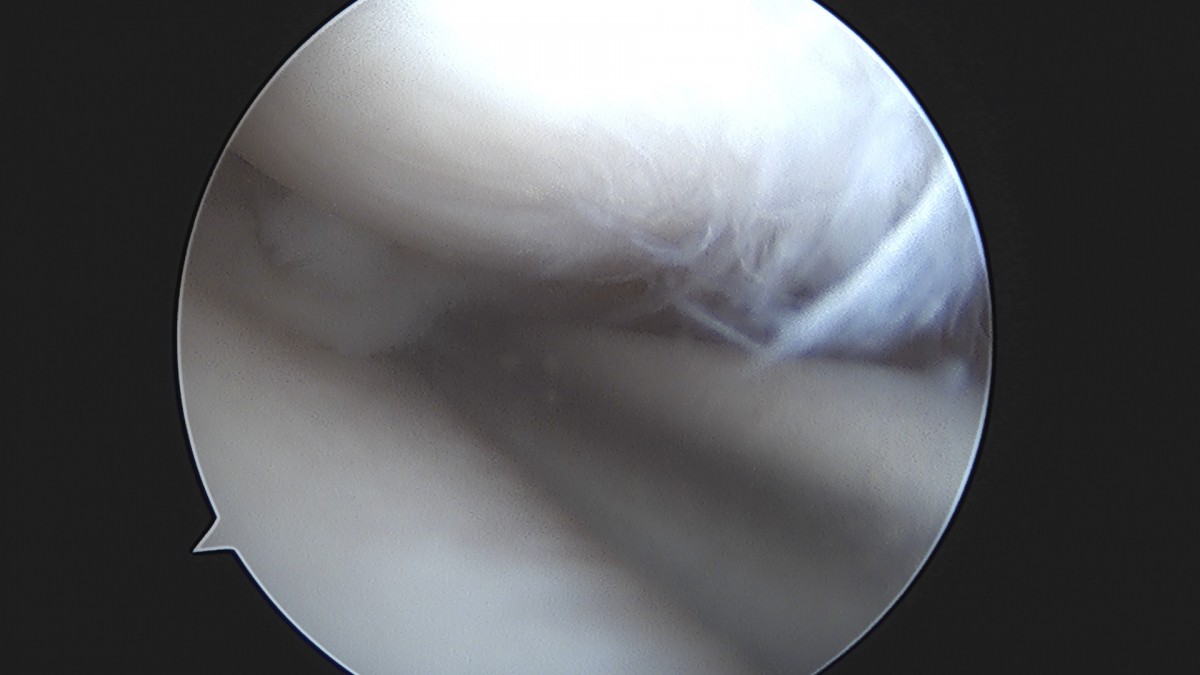

이재상원장님 무릎 반월상 연골판 절제술 장영O 환자

작성자 최고관리자 댓글 0건 조회 369회 작성일 25-09-16 16:02

dae765e4d9ac96aee867c9d6292d8784_1758006134_9328.jpg